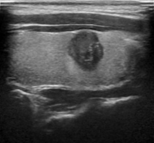

Figure 6 illustrates the segmentation outcomes attained with different neural networks using the same dataset. The enhanced U-Net network proposed in this study is evaluated alongside expert gold standards, Swin-Unet, U-Net, and other well-known network models. The segmentation results from the Swin-Unet network show jagged edges and less smooth nodule edge segmentation, leading to suboptimal outcomes. In the case of U-Net, there are evident under-segmentations with significant discrepancies in the segmented area of some nodules, resulting in inaccurate segmentation results. However, the use of the improved U-Net network introduced in this research produces smoother edges of the segmented thyroid nodules, and the edge contours more closely align with those of the expert gold standard. Moreover, the errors in shape and segmented area are smaller compared to those seen with U-Net and Swin-Unet. The findings suggest that the improved U-Net network provides superior performance in thyroid nodule segmentation.